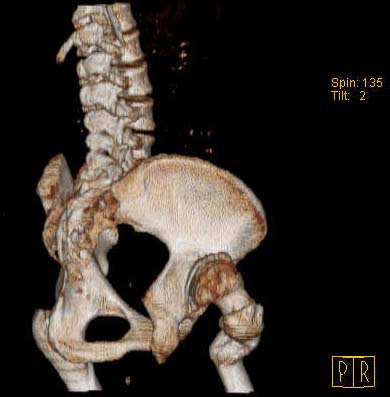

Уважаемые коллеги!Женщина, 35 летВ прошлом по поводу врожденного вывиха бедра перенесла операцию остеотомии по Шанцу

с удлинением правой ноги за счет бедра на уровне диафиза. В последнее время прогрессируют боли в правом тазобедренном суставе, порочное положение правой ноги, затруднена ходьба.Вопросы:1) Целесообразно ли эндопротезирование правого тазобедренного сустава?2) Целесообразный ли следующие действия: канал бедренной кости предполагаем вскрыть для введения ножки протеза на высоте угловой деформации, предполагаем низведение большого вертела с мышцами; протез будет подобран индивидуально, предполагается умеренная версия?В приложении рентгенограммы и трехмерная КТ.В цветном и более качественном варианте КТ размещена здесь